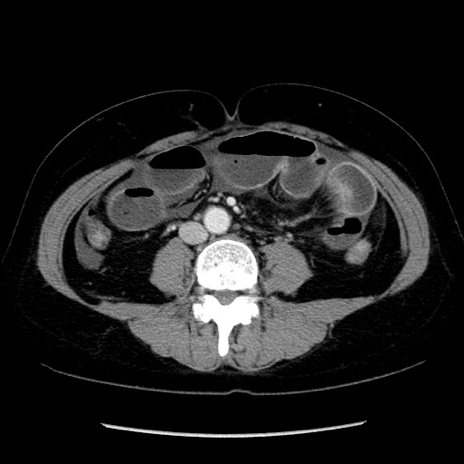

冠状断像

症例6(横断像)

【症例】50歳代女性

【既往歴】卵巣癌術後(8年前に当院で卵巣摘出)

【身体所見】 意識清明、腹部:平坦、腸蠕動音→、やや硬、下腹部自発痛・圧痛あり、反跳痛あり、筋性防御なし。

【データ】WBC 16000、CRP 0.01